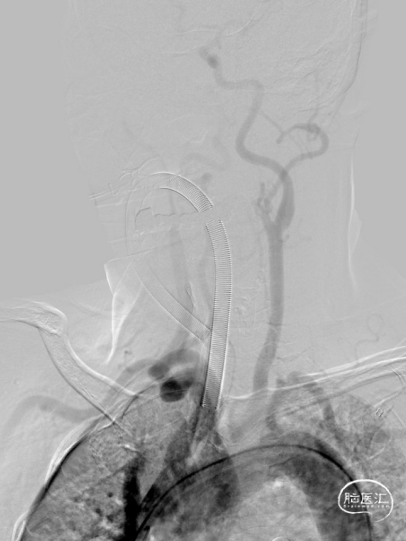

术前造影:

造影显示RICA:C1段起始部闭塞,残端呈锥形,TICI分级0级;RMCA未显影,远端由RACA经皮层支少量代偿,ASITN分级1-2级。

患者血管路径迂曲,经Simon2导管采用交换技术将8F导引导管内衬多功能导管,反复尝试均无法进入RCCA,后更换为Super Stiff导丝支撑,将8F导引导管送至RCCA远端。

将Catalyst7 132中间导管经导引导管送至于RICA C1段起始部闭塞处,采用ADAPT技术自C1段至C4段反复抽吸取栓,取出大量暗红色血栓。